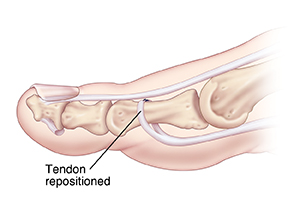

Tendon release

This treatment helps release the buckled joint. The bottom (flexor) tendon may be repositioned to the top of the affected toe (flexor tendon transfer). Sometimes, the top or bottom tendon is released but not repositioned (tenotomy).

| Flexor tendon transfer. |